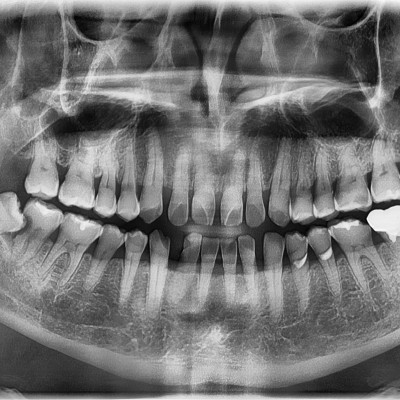

#18,28,38,48 사랑니 발치 #18,28,38,48 사랑니 발치 구강 외과 전문의가 당일 발치했습니다. ------------------..

작성자 이턱이 작성일 02-02 조회 4